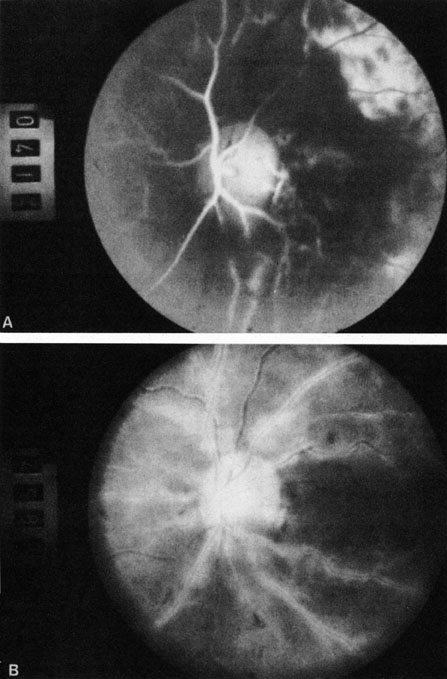

Fig. 3. A: Cilioretinal artery obstruction showing opacity of the retina in the area of obstruction. B: The cilioretinal artery has begun to fill after the branches of the central retinal artery but is still not completely filled at this point in the angiogram.

Fig. 5. A: Ischemic optic neuropathy in a patient with giant cell arteritis. B and C: Intravenous fluorescein angiography demonstrates delayed filling of the lateral posterior ciliary artery.